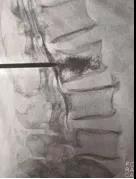

手術(shù)中情況

4月21日,我院骨科孫守全專家小組為老人進(jìn)行了PKP手術(shù),術(shù)后當(dāng)天老人腰背部疼痛銳減,己能坐起吃飯。術(shù)后第二天就能下床大小便,生活已能基本自理。七天后,老人順利出院!按照常規(guī)治療方法,需臥床三個(gè)月,還有可能出現(xiàn)尿路感染、肺部感染等等一系列并發(fā)癥。這結(jié)果與現(xiàn)在相比真有天壤之別!據(jù)了解,PKP手術(shù)為脊椎的微創(chuàng)手術(shù),手術(shù)時(shí)間短、創(chuàng)傷小,出血少,止痛效果明確,恢復(fù)比較快。尤其是對(duì)于高齡衰弱的患者而言,采用PKP手術(shù)治療,患者承擔(dān)的手術(shù)風(fēng)險(xiǎn)極大地減少,并且避免了長(zhǎng)期臥床所導(dǎo)致的潛在并發(fā)癥。但該手術(shù)部位鄰近脊柱總神經(jīng),需要施術(shù)者嫻熟的手術(shù)技巧和細(xì)心大膽的手術(shù)操作。我院骨科在濰坊市較早引入椎體成形術(shù),目前已經(jīng)為近千名老人解除了"腰痛"病痛。